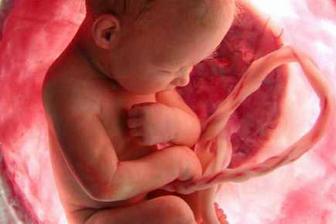

23.5. pro průkazku + odběr krve + utz 11+0 mimisek 4,2cm